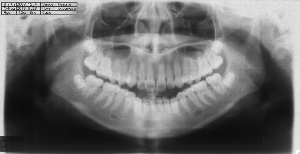

ステップ3. レントゲン (パノラマ,セファロ)撮影 口腔内写真撮影

横顔のレントゲン及び実際の横顔のデジタル画像のコンピューターへの入力の後、

あなたの骨格、歯の状態に合わせて、治療を受けた場合の横顔の変化のシュミレーションを行います。

ステップ3. レントゲン(パノラマ、セファロ)撮影・口腔内写真撮影